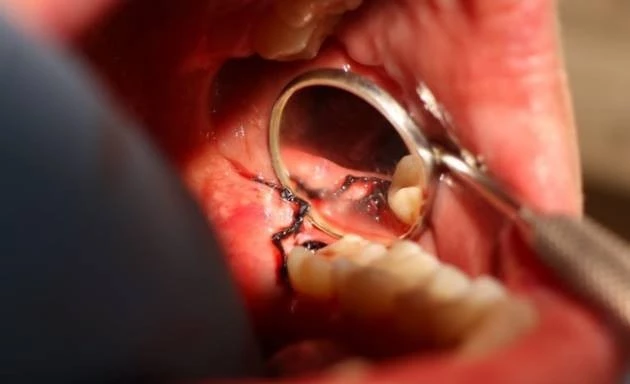

Poniżej przedstawiamy zabieg usunięcia zatrzymanego zęba mądrości wykonany przez specjalistę chirurgii stomatologicznej - dr Tomasza Kozioła, który polegał na znieczuleniu miejscowym, odsłonięciu zęba, zniesieniu blaszek kostnych z okolicy zęba, odcięciu korony i jej usunięciu, rozdzieleniu korzeni i ich usunięciu oraz zszyciu rany.